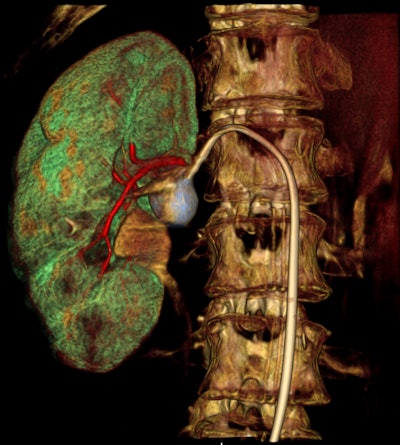

Image of a renal aneurysm acquired with Toshiba's Infinix-i Rite Edition digital radiography system."We focus on patient comfort, so our philosophy is to move neither the patient nor the table, but the hardware," noted René Degros, the company's European x-ray business unit manager.

As interventional procedures become more complex, advanced 3D acquisition is becoming increasingly important, he pointed out. There is also an emphasis on flexible, responsive technology, so the C-arm's lateral movement allows it to be moved out of the way during a procedure. During lung biopsies, for example, the unit can be flipped through 180ï‚° to place the flat-panel detector beneath the patient table.